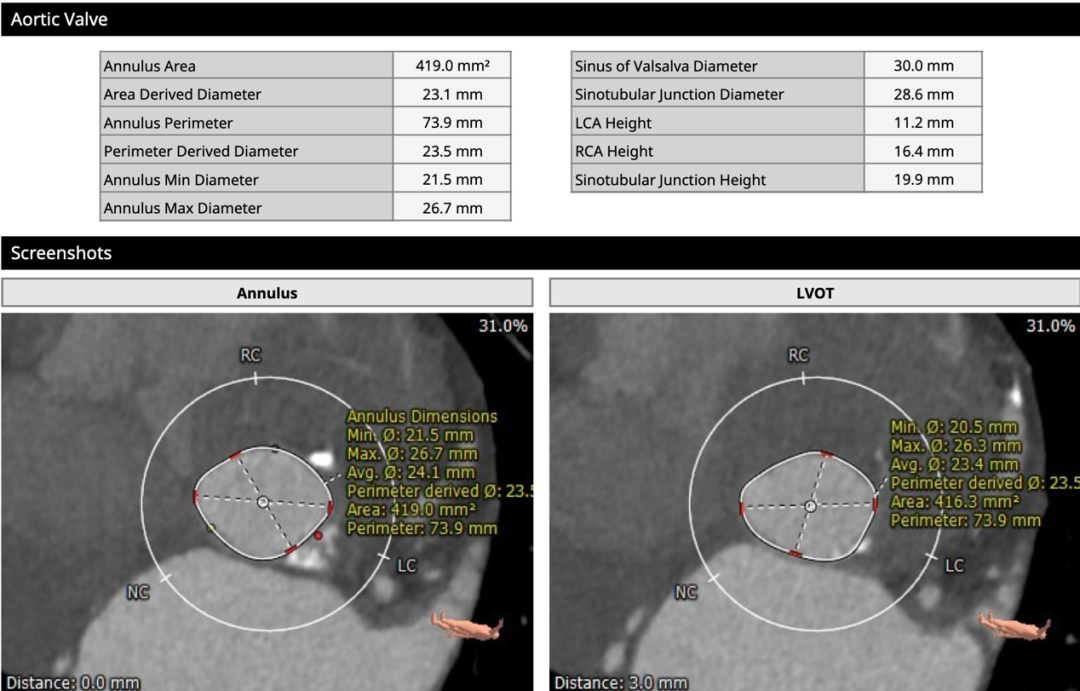

术前CT

为三叶式主动脉瓣,瓣叶钙化较重,瓣环周长获得平均直径23.5mm,左右冠脉开口高度分别为11.2和16.4mm。瓣叶冗长,左冠开口水平可见瓣叶,左冠有堵塞风险。双侧股动脉走行流畅,无明显钙化迂曲,左右最细处分别为6.5和6.6mm。

手术策略

经心脏团队讨论后,拟全麻食道超声监测下,行左冠保护,经右主入路植入23mm SAPIEN 3瓣膜。